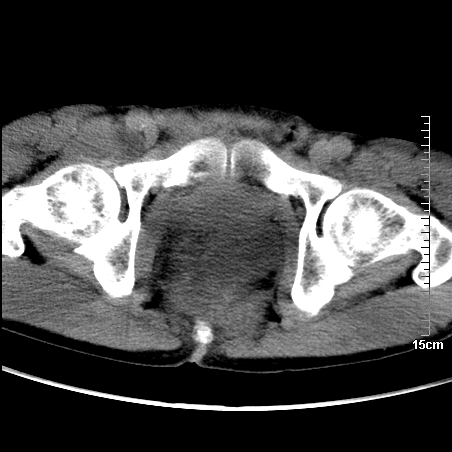

增强:

1、骶尾部巨大软组织肿块,部分骶尾骨以被软组织肿块代替,呈不规则侵蚀;病变突向盆腔内;增强扫描病变呈不均质强化;首先考虑脊索瘤。不支持的一点就是病变内无钙化。

2、发生于骶尾椎者须与骨巨细胞瘤鉴别,骨巨细胞瘤一般发在上疗骶椎,肿瘤内无钙化,一般无侵袭性生长的表现。